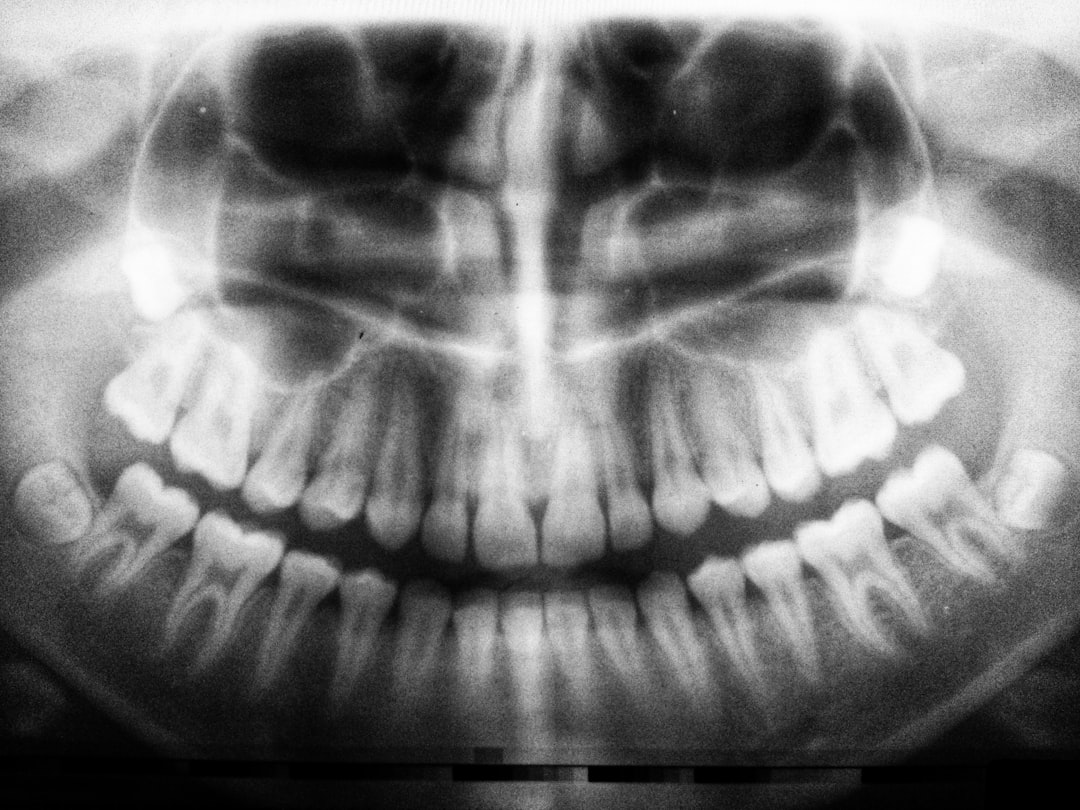

임플란트 치료의 과정은 크게 3단계로 나누어집니다. 첫째, 초기 상담 및 진단 단계입니다. 이때 전문가는 환자의 구강 상태와 뼈의 밀도를 평가하여 치료 계획을 수립합니다. 이 과정에서 소소한 검사가 이루어지며, 환자의 불안감을 최소화하는 것이 중요하죠.

둘째, 수술 단계에서는 인공 치아 뿌리가 턱뼈에 심어지는 수술이 진행됩니다. 이 단계는 보통 한 번의 수술로 끝내지 않고, 치유 과정을 거쳐야 합니다. 예를 들어, 치아와 뼈가 잘 융합되기까지 몇 개월이 걸릴 수 있습니다. 이를 통해 여러분은 임플란트 기간 단축, 가능성은?을 고민하게 됩니다.